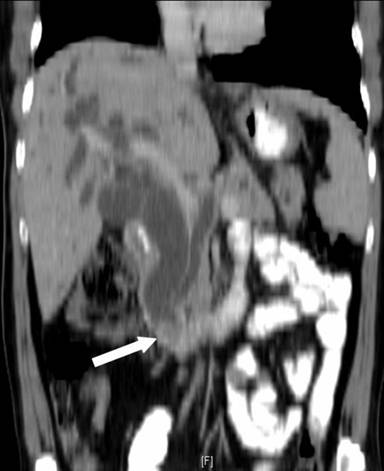

He underwent a pancreaticoduodenectomy. On transecting the neck of the pancreas, there was a small duct (4 mm) on the cut surface anterior to the portal vein. While dividing the bulky uncinate process, which seemed to extend posteriorly and to the left of the portal vein, a dilated duct (10 mm) was encountered. This dilated duct was found to be continuous with the main pancreatic duct posterior to the portal vein. The anterior duct in the neck of the pancreas terminated a few centimeters within the body of the pancreas without communication with the main pancreatic duct. The large pancreatic duct encountered in the uncinate process resection was closed with interrupted 5/0 polypropylene sutures. The neck of the pancreas anterior to the portal vein was excised up to the dilated main pancreatic duct, well to the left of the portal vein. The main pancreatic duct was laid open and a side to side pancreaticojejunostomy was performed. The patient made an uneventful recovery from the surgery. A review of the CT scan showed the double ducts encircling the portal vein with the main pancreatic duct lying posteriorly to the portal vein (Figures 1, 2, 3 and 4).

Figure 3. White arrow showing the site of obstruction. |